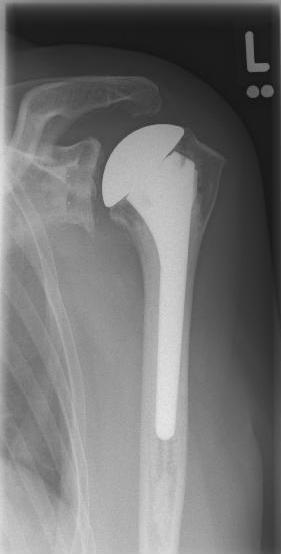

Short stem prostheses as modern implants for omarthrosis and acetabular wear

left: X-ray image of a short-shaft prosthesis

right: Short-shaft prosthesis (Affinis Short type, Mathys company)